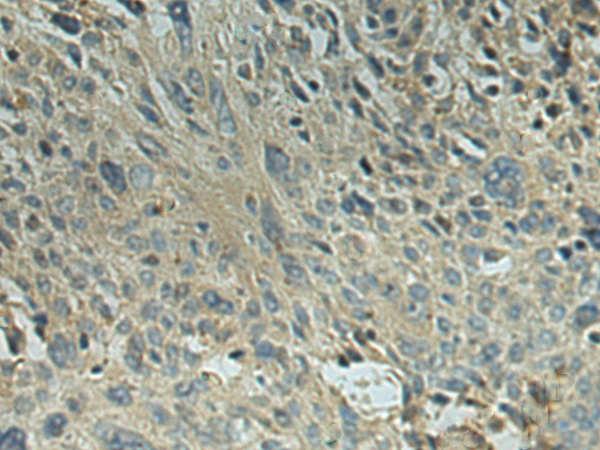

分类: 科研抗体货号: P02867别名: DHPR; PKU2; HDHPR; SDR33C1应用: WB,IHC反应种属: Human, Mouse, Rat